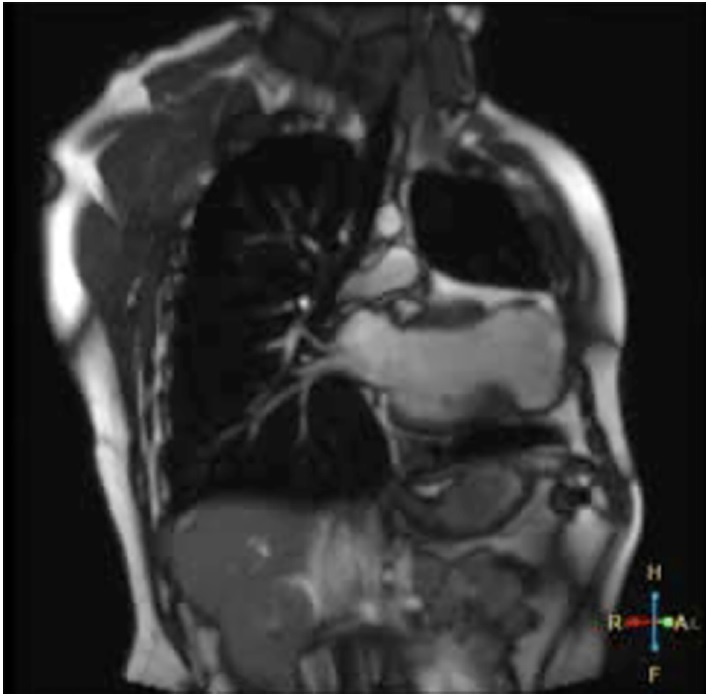

Presentamos un paciente de sexo masculino de 30 años, con antecedentes de miocardiopatía dilatada isquémico-necrótica no ateroesclerótica, con fracción de eyección ventricular izquierda (FEVI) reducida (35%) y aneurisma ventricular (Figura 1) por lesión iatrogénica, extrínseca, tras la sutura de la arteria descendente anterior, luego de una herida de arma de fuego y cirugía de urgencia. Evoluciona posteriormente con varias internaciones por episodios recurrentes de taquicardia ventricular monomorfa sostenida (TVMS) (Figura 2a) por lo que se decide colocación de un dispositivo cardiodefibrilador implantable (CDI) y ablación del sustrato, con evolución favorable.

Fig. 1 Corte coronal de resonancia magnética en secuencia T2 donde se evidencia dilatación ventricular izquierda, la presencia de saco aneurismático apical, adelgazamiento miocárdico y señal de baja intensidad.